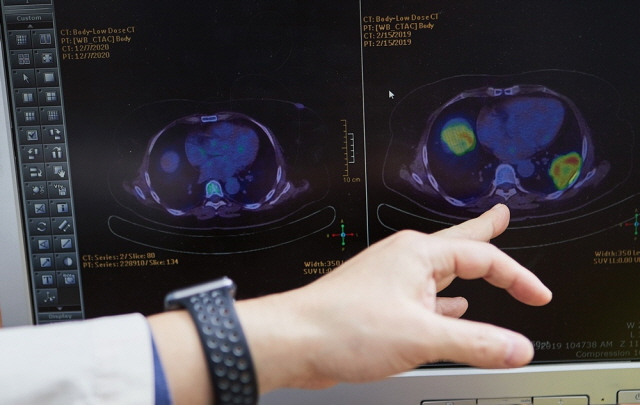

심 교수가 표적항암치료를 받은 후 암이 완전히 사라진 환자 사례를 설명하고 있다./사진=신지호 헬스조선 기자